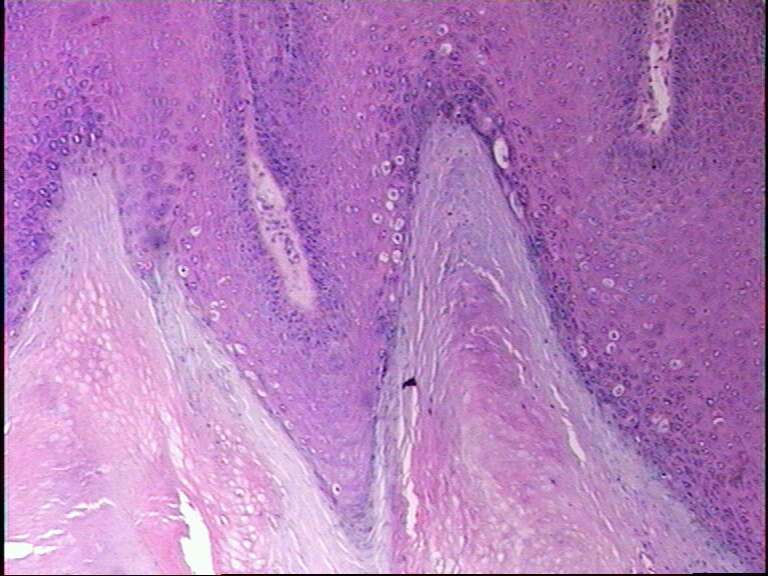

男38岁,手指肿物一年

寻常疣

最后一张典型的寻常疣构型

寻常疣 肉眼间 皮肤局限性乳头状突起新生物。

镜下 表皮棘层增生,颗粒层增厚,角化亢进及角化不全,真皮乳头瘤病。颗粒层细胞空泡变性,其核内或胞质内有均质性嗜酸性蛋白小体形成,周围有空晕。角化不全的细胞科堆积成小山包样外观。

乳头瘤样增生,空泡化细胞,典型寻常疣!最后一张典型的寻常疣构型!

典型的寻常疣病理改变。